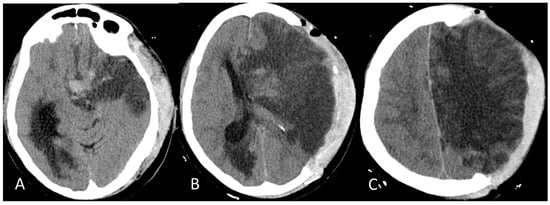

A 46-year-old Caucasian woman was admitted to the Emergency Medicine Unit at the local hospital with a complaint of sudden weakness in the right side of the body and speech difficulty on 4 June 2021. The patient was in good general clinical condition and with no significant pathologies of both congenital and acquired origins in her past medical history or upon physical examination. Her family history was also negative for the occurrence of thrombotic events. In December 2020, she developed a SARS-CoV-2 infection in a mild form. On 27 May 2021, she received an anti-COVID-19 vaccination with the first dose of ChAdOx1 nCoV-19. Following a head Computed Tomography (CT) and CT angiography of the cerebral vessels and the intracranial and epiaortic tracts, a thrombotic occlusion of the left-middle cerebral artery was revealed. Laboratory blood tests, performed in the local hospital, showed the presence of thrombocytopenia. For this reason, the patient was not eligible for intravenous fibrinolysis, and she was therefore transferred, on 5 June 2021, to the Annunziata Hospital, Cosenza, which is equipped with a Second Level Stroke Unit, for possible mechanical thrombectomy. Upon arrival in the emergency room, the patient appeared alert, with global aphasia, central-type right seventh cranial nerve deficit, palsy of the right upper limb, and severe paresis of the right lower limb, with an NIHSS score equal to 18. Her vital signs were in the normal range (BP 110/79 mmHg; HR 68 bpm R; axillary temperature 36.3 °C; O2 saturation 98% at room temperature). Blood analysis revealed the presence of thrombocytopenia, an increase in the D-dimer compared to reference values, and fibrinogen and glycemia in the normal value range (Table 1). A brain CT showed an extensive hypodense area suggestive of acute ischemic lesion with a frontal–cingulate cortical–subcortical site, temporo-insular, and marginally left parietal. Initial disappearance of the cortico–subcortical interface (ASPECT score: 4), smoothing of the left fronto-temporo-insulo-parietal cortical sulci, hyperdensity of the supraclinoid tract of the left siphon and the A1 and M1 ipsilateral tracts, of probable thrombotic significance, were evident, as is shown in Figure 1A–D.

Figure 1. Brain CT on day one. (A) Vessel hyperdensity on the left of thrombotic significance and bifurcation of the siphon, the M1, and the A1–A2 tracts; (BD): Cortico–subcortical temporo-insular and fronto-cingulum-parietal hypodensity. ASPECT score 4.